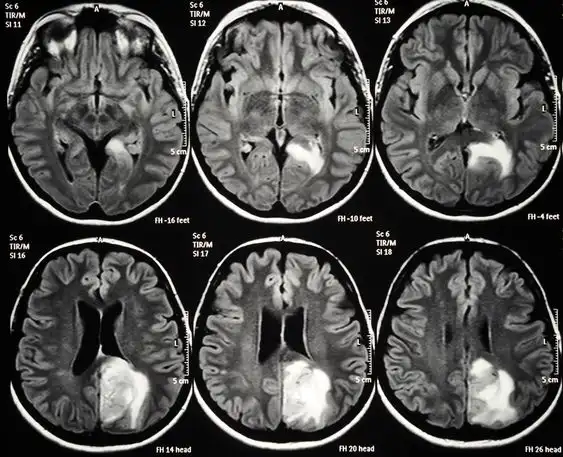

4. 진단은 MRI, CT 스캔을 통해 이루어지며, 조직 검사로 확진합니다.

교모세포종의 진단은 주로 고해상도의 영상 진단 도구인 MRI 또는 CT를 통해 이루어집니다.

이러한 검사를 통해 종양의 위치, 크기 및 주변 조직과의 관계를 정확히 평가할 수 있습니다.

또한, 최종적인 진단을 위해서는 조직 검사가 필수적으로 수행됩니다.